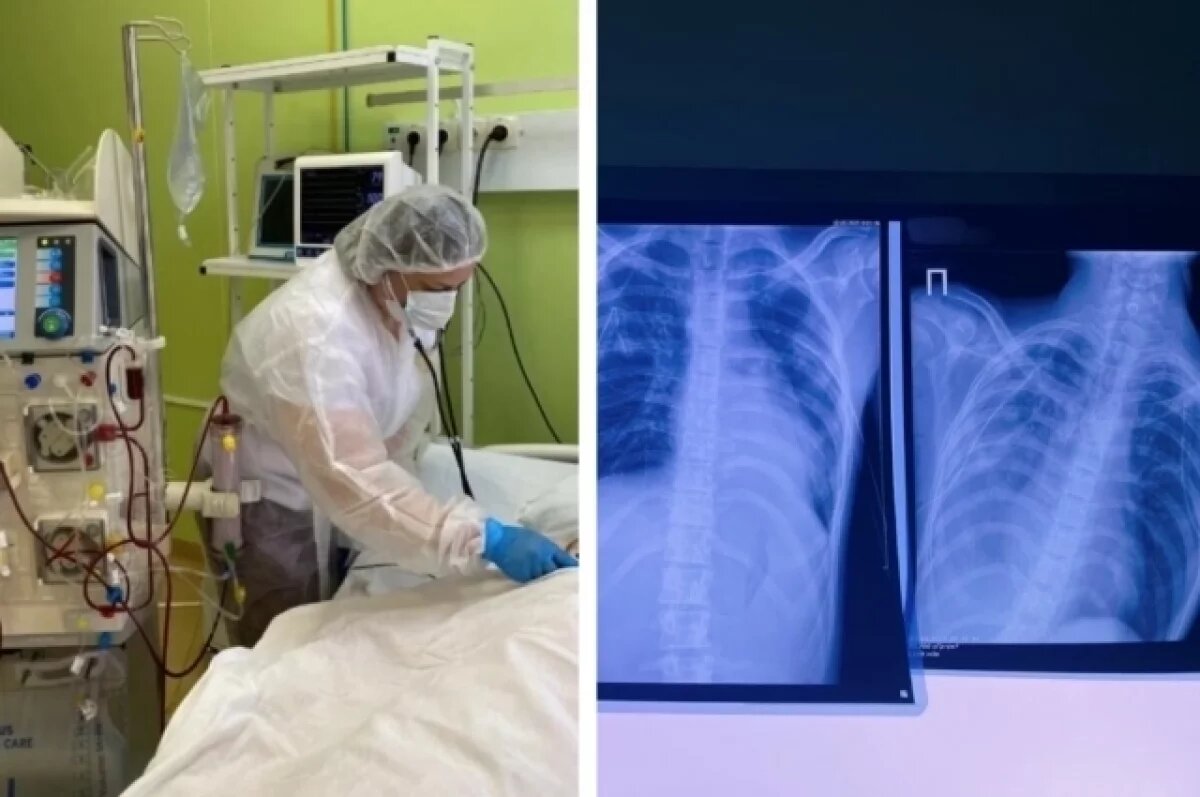

На опубликованных сотрудниками регионального минздрава кадрах – пугающие рентенговские снимки с явными затемнениями на лёгких. Трудно поверить, что они принадлежат школьникам.

Несколько лет вейпинга привели к тому, что в лёгких юного кировчанина образовались буллы (воздушные полости, окружённые тонкими стенками). Состояние подростка стало критическим, когда они внезапно разорвались, вызвав двусторонний пневмоторакс – состояние, которое сопровождается болью в груди и одышкой с ощущением, что в груди что-то перемещается.